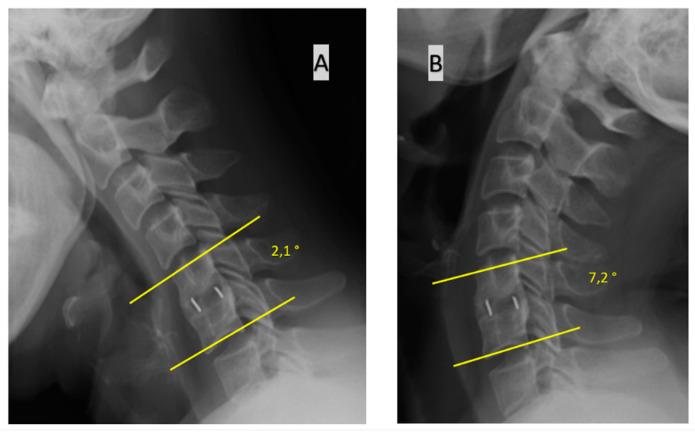

Most surgical procedures performed on account of degenerative disease of the cervical spine involve a discectomy and interbody fixation. Bone fusion at the implant placement site is evaluated post-operatively. It is agreed that computed tomography is the best modality for assessing bone union. We evaluated the results obtained with various methods based solely on conventional radiographs in the same group of patients and compared them with results obtained using a method that is a combination of CT and conventional radiography, which we considered the most precise and a reference method. We operated on a total of 170 disc spaces in a group of 104 patients. Fusion was evaluated at 12 months after surgery with five different and popular classifications based on conventional radiographs and then compared with the reference method. Statistical analyses of test accuracy produced the following classification of fusion assessment methods with regard to the degree of consistency with the reference method, in descending order: (1) bone bridging is visible on the anterior and/or posterior edge of the operated disc space on a lateral radiograph; (2) change in the value of Cobb's angle for a motion segment on flexion vs. extension radiographs (threshold for fusion vs. pseudoarthrosis is 2°); (3) change in the interspinous distance between process tips on flexion vs. extension radiographs (threshold of 2 mm); (4) change in the value of Cobb's angle of a motion segment (threshold of 4°); (5) change in the interspinous distance between process bases on flexion vs. extension radiographs (threshold of 2 mm). When bone union is evaluated on the basis on radiographs, without CT evidence, we suggest using the "bone bridging" criterion as the most reliable commonly used approach to assessing bone union.

摘要

大多数因颈椎退行性疾病而进行的外科手术都包括椎间盘切除术和椎间融合内固定术。术后需评估植入部位的骨融合情况。目前公认计算机断层扫描是评估骨愈合的最佳方式。我们仅基于传统X线片,评估了同一组患者采用各种方法所获得的结果,并将其与采用CT和传统X线摄影相结合的方法所获得的结果进行比较,我们认为后者是最精确的参考方法。我们对104例患者的总共170个椎间盘间隙进行了手术。术后12个月,采用基于传统X线片的五种不同且常用的分级方法评估融合情况,然后与参考方法进行比较。对检测准确性的统计分析得出了以下关于融合评估方法与参考方法一致性程度的分级,从高到低依次为:(1)在侧位X线片上,手术椎间盘间隙的前缘和/或后缘可见骨桥形成;(2)屈伸位X线片上运动节段的Cobb角值变化(融合与假关节形成的阈值为2°);(3)屈伸位X线片上棘突尖端间棘间距离的变化(阈值为2mm);(4)运动节段Cobb角值的变化(阈值为4°);(5)屈伸位X线片上棘突根部间棘间距离的变化(阈值为2mm)。当基于X线片评估骨愈合情况而无CT证据时,我们建议使用“骨桥形成”标准作为评估骨愈合最可靠的常用方法。